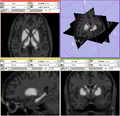

2. Generating BRAINSCut model for subcortical structures: caudate, putamen, thalamus, and hippocampus. DONE

3. Verifying generated model by comparing manual traces. DONE